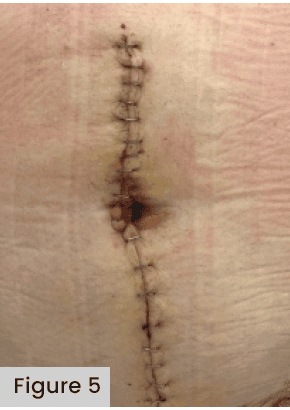

A meta-analysis comparing wound dressings after hip/knee arthroplasty demonstrated that an antimicrobial dressing is optimal for preventing infection (Kuo et al, 2021); the authors also warned that, if NPWT is used, surgeons must be aware of the increased incidence of skin blistering formation [Figure 5]. The data from 21 studies, encompassing 12 dressing types applied across 7,293 total joint arthroplasties identified the highest incidence of blisters occurred when using negative pressure wound therapy (OR 9.33; 95% CI 3.51-24.83) versus gauze. They recommended further research focusing on alginate versus hydrofiber and hydrocolloid dressings to determine the optimal dressing to reduce blisters.